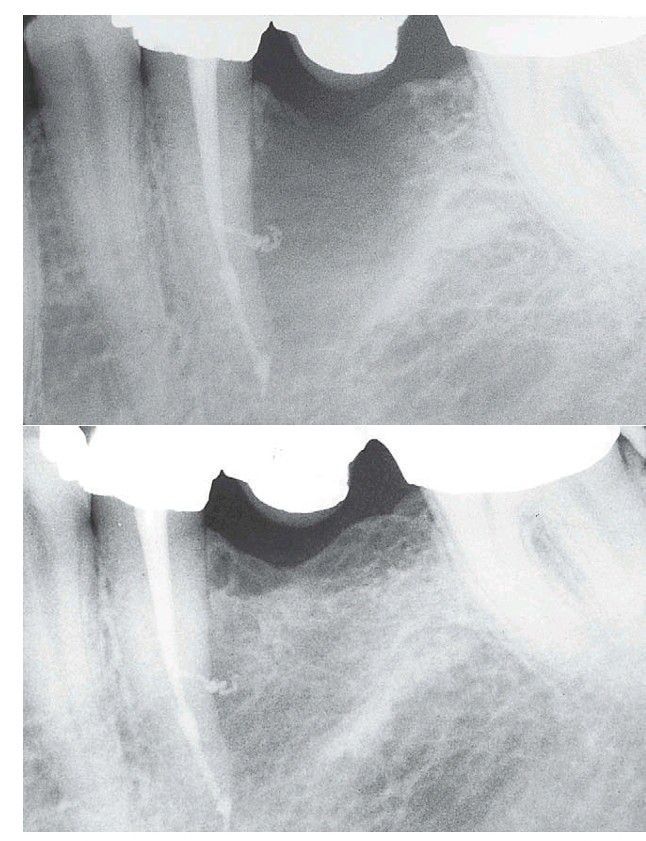

Bony defect in alveolar bone

A large, bony defect associated with tooth #20 healed after endodontic therapy. The tooth was nonvital, and no significant peri odontal probing depth indicated pulpal disease.